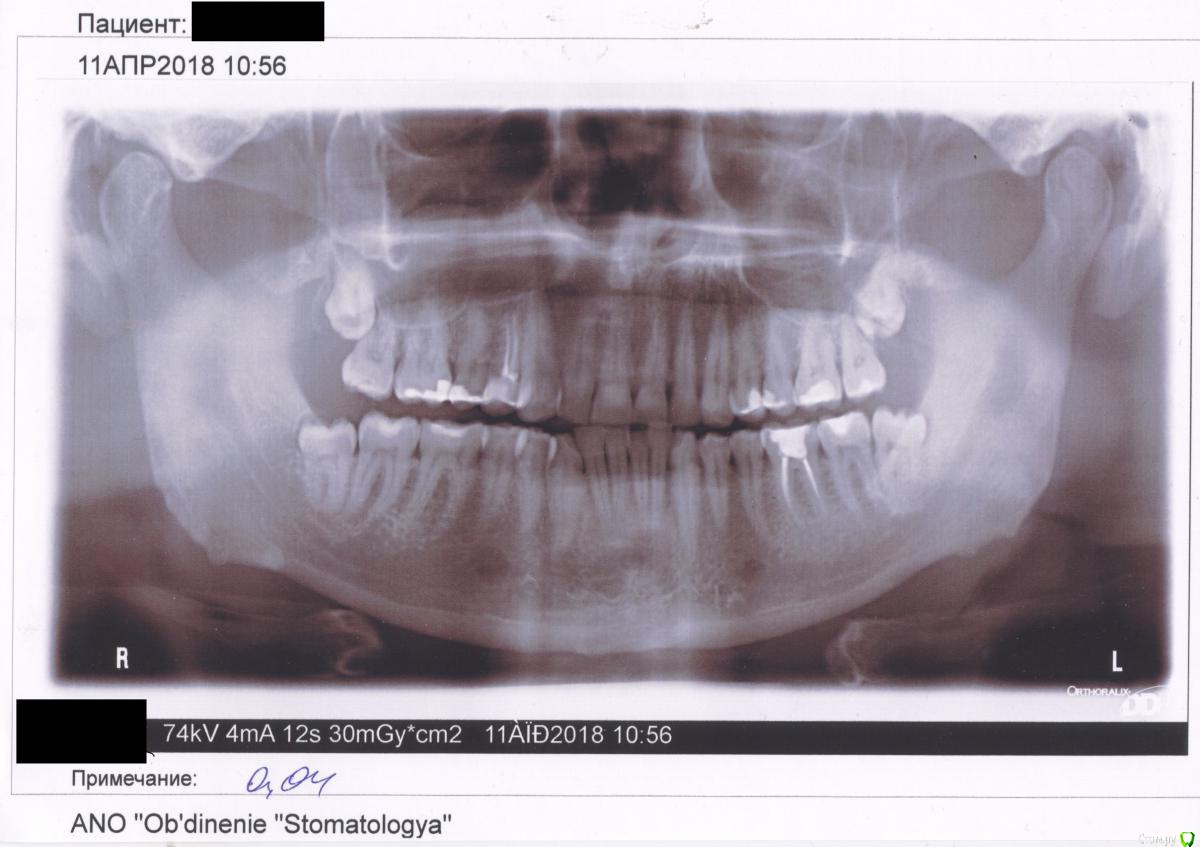

Vivekananda Опубликовано 21 мая, 2018 Поделиться Опубликовано 21 мая, 2018 (изменено) Добрый день! Пишет мужчина, возраст 40 лет, Екатеринбург. В начале апреля 2018 начал слегка болеть 6й зуб нижней челюсти слева. 11 апреля врач-стоматолог сделала снимок и сказала, что зуб в порядке - вероятно, боль возникает по причине того, что на него оказывает давление зуб мудрости. Однако, не будучи хирургом, она не была уверена, и направила к зубному хирургу. Я пошел к хирургу в клинику на ул. Пушкина, 1 (Екатеринбург). Он посмотрел снимок, зубы, и сказал, что в принципе нужно удалять зубы мудрости, но боль возникает не из-за сдавливания, а из-за чего-то другого. Возможно, преходящее воспаление (т.к. болит не сильно и с перерывами по неделю-две). Сказал сходить к зубному врачу в их клинике, чтобы сначала выяснить причины боли, разобраться с ней сначала. Зубной врач сказала, что причин для рассверливания зуба не видит, дала рецепт на таблетки от боли. Сказала, что не советует удалять зубы мудрости, т.к. у операции могут быть серьезные последствия, а необходимость её не очевидна. Прошло две недели, и опять пару дней беспокоил 6-й зуб. Боль очень легкая, большую часть времени он меня не беспокоит. В зубе запломбированы каналы, насколько я понял - на снимке они "заасфальтированы". Последние дней 10 зуб не беспокоил. Вопрос - судя по снимку, нужно ли удалять зубы мудрости в нижней челюсти? Может ли зуб мудрости так хитро давить, что болит не 7-й, а именно 6-й зуб, которого он даже не касается? Заранее благодарю за ответ.(И еще микро-вопрос - к кому лучше обратиться в Екатеринбурге, чтобы все точно выяснить?) Изменено 21 мая, 2018 пользователем Vivekananda Ссылка на комментарий

red_butler Опубликовано 21 мая, 2018 Поделиться Опубликовано 21 мая, 2018 Шестой зуб требует повторного лечения 1 Ссылка на комментарий

St. Опубликовано 24 мая, 2018 Поделиться Опубликовано 24 мая, 2018 Зубам мудрости в челюстях нет места, полностью они не прорежутся, но и соседей не сильно толкают. Основная проблема что если из десны выступает только часть зуба, то под десну может забиваться еда которую невозможно вычистить оттуда и зубы начинают портиться и могут потом болеть. Планово в будущем лучше удалить.В 6 внизу каналы заполнены материалом не до конца, нужно их перелечить 1 Ссылка на комментарий